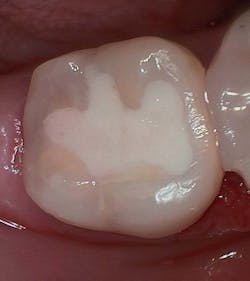

Figure 3 shows the final restoration immediately after placement. Figure 4 shows the final restoration of an initial caries lesion on the buccal. The clinician anticipated maturation of the glass-hybrid in choosing a lighter shade of A2, which initially appeared much too light. A slightly darker shade may have been more appropriate.

Figure 5 is a 36-month follow-up bitewing radiograph demonstrating excellent support of the significantly undermined enamel and deposition of secondary dentin in the mesial pulp horns. Figures 6 and 7 show the occlusal and facial restorations respectively after 18 months. Notice the improvement in shade.